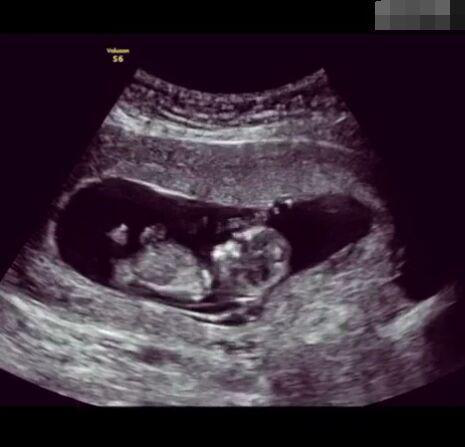

那些做了B超檢查確定胎兒男女,生下來后發(fā)現(xiàn)不對的,多半是因為在B超檢查時寶寶太調(diào)皮,以致影響了檢查準(zhǔn)確性。就比如說,有的女寶寶在媽媽肚子里玩自己的臍帶,把臍帶夾到了兩腿中間,B超就有一定幾率拍出來好像是男寶寶的特征,導(dǎo)致被誤認(rèn)為是男孩子。還有些男寶寶過分害羞,在做B超時雙腿緊緊并攏,醫(yī)生也很難判斷男女,只好大致猜測是女孩,就又造成了誤會。因此,B超亦不是萬能的。